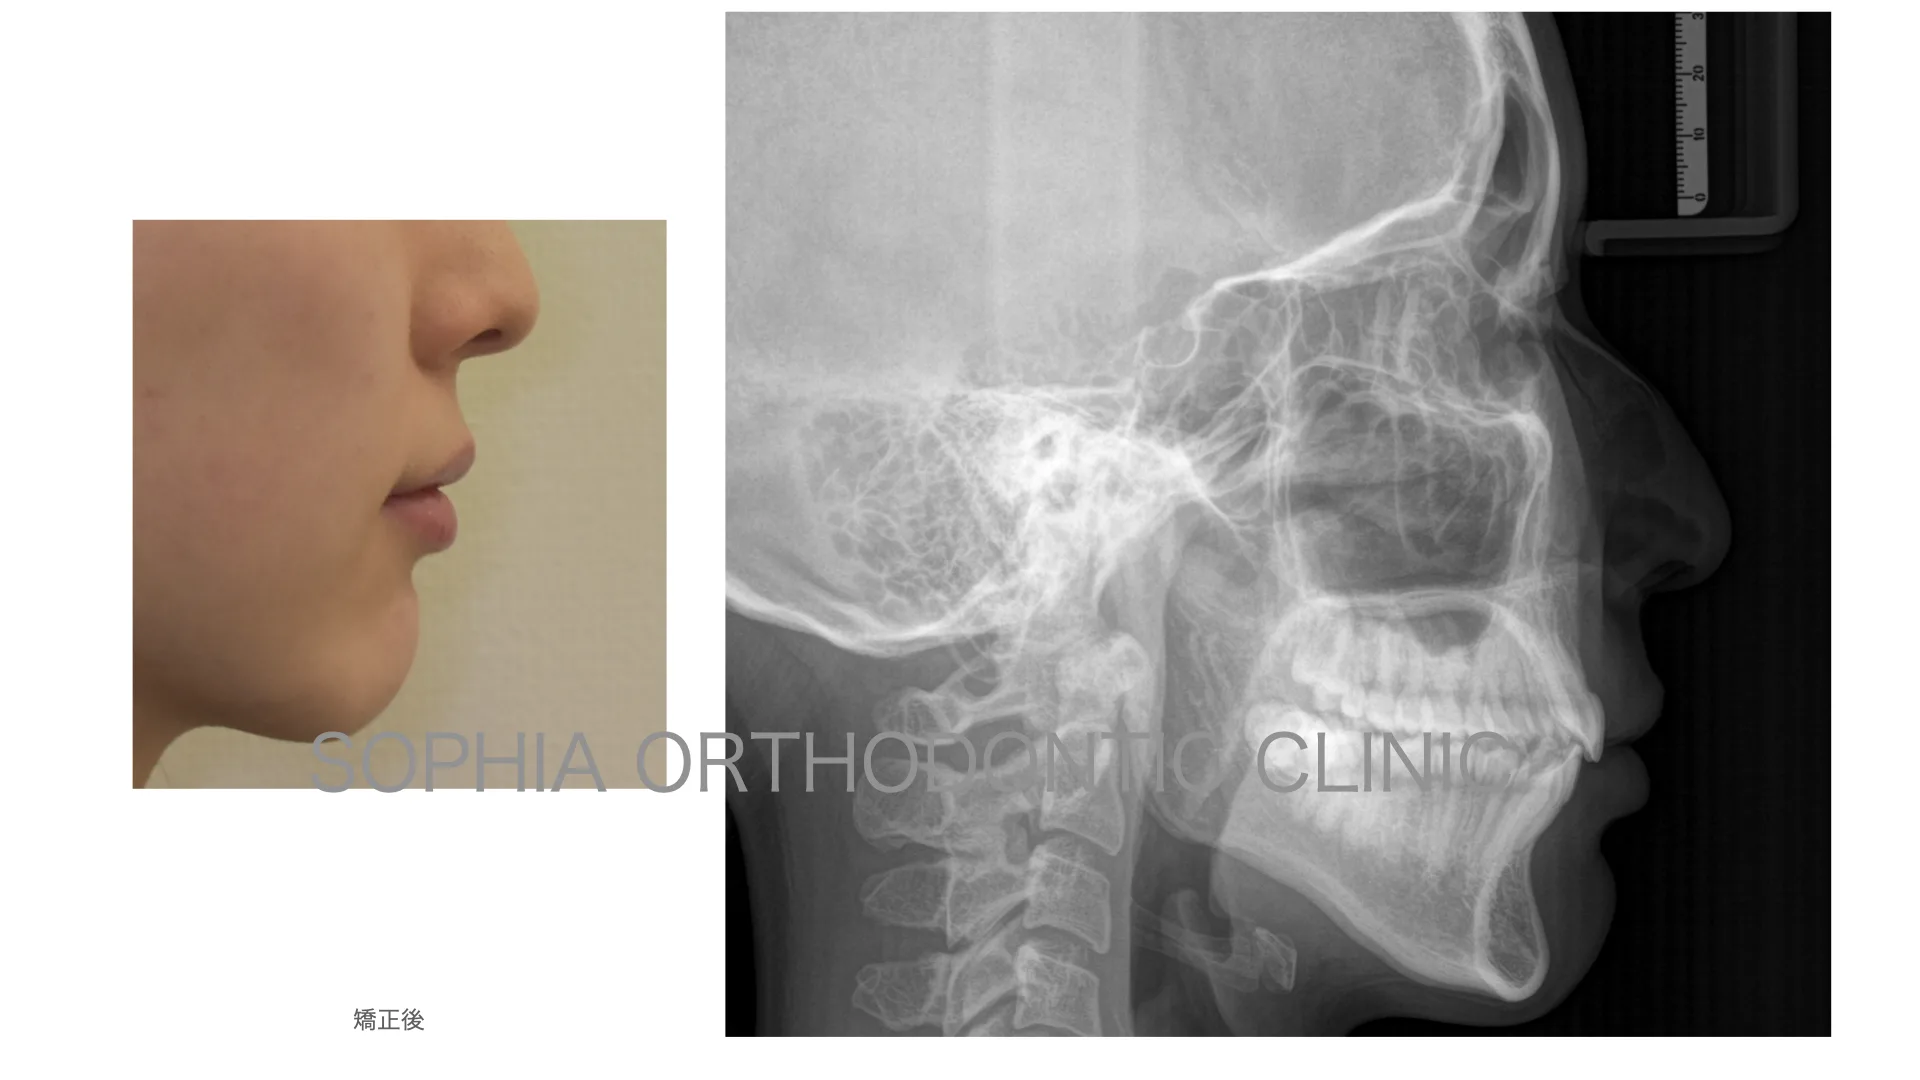

症例 上顎前突 抜歯